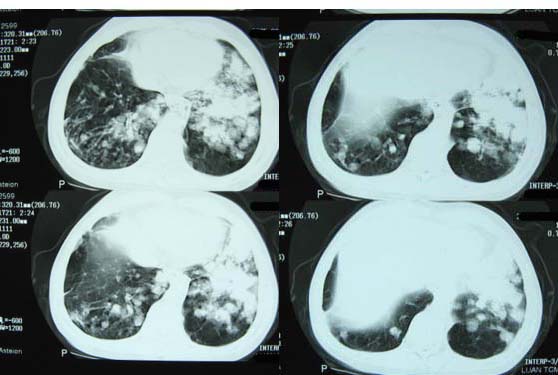

1肺转移瘤 2肝门区圆形软组织影,考虑淋巴结转移

1、双肺多发转移瘤可能性大,建议进一步检查。

2、支气管扩张

右上肺后段及左上肺舌段片状影,考虑双肺结核。

双肺弥漫性结节影,考虑双肺转移性肿瘤。